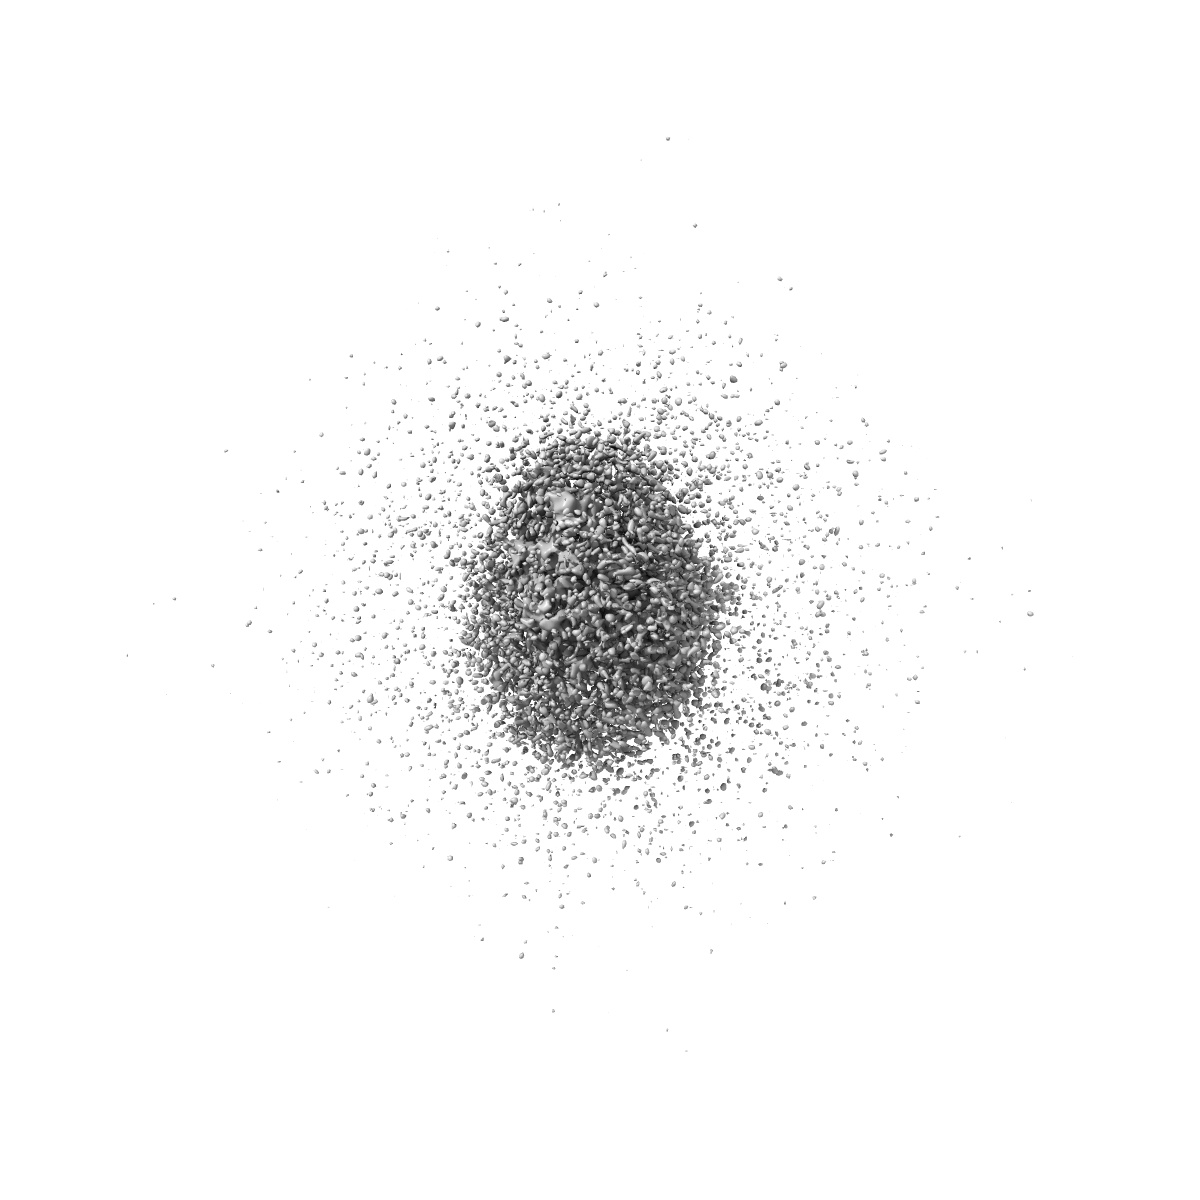

Cryo-EM Structure of the wild-type human serotonin transporter in complex with ibogaine and 15B8 Fab in the inward conformation

Sample Organism: Mus musculus, Homo sapiens

Sample: Human serotonin transporter in complex with Fab bound to ibogaine

Fitted models: 6dzz

Serotonin transporter-ibogaine complexes illuminate mechanisms of inhibition and transport.

Coleman JA, Yang D, Zhao Z , Wen PC , Yoshioka C, Tajkhorshid E, Gouaux E

(2019) Nature , 569 , 141 - 145